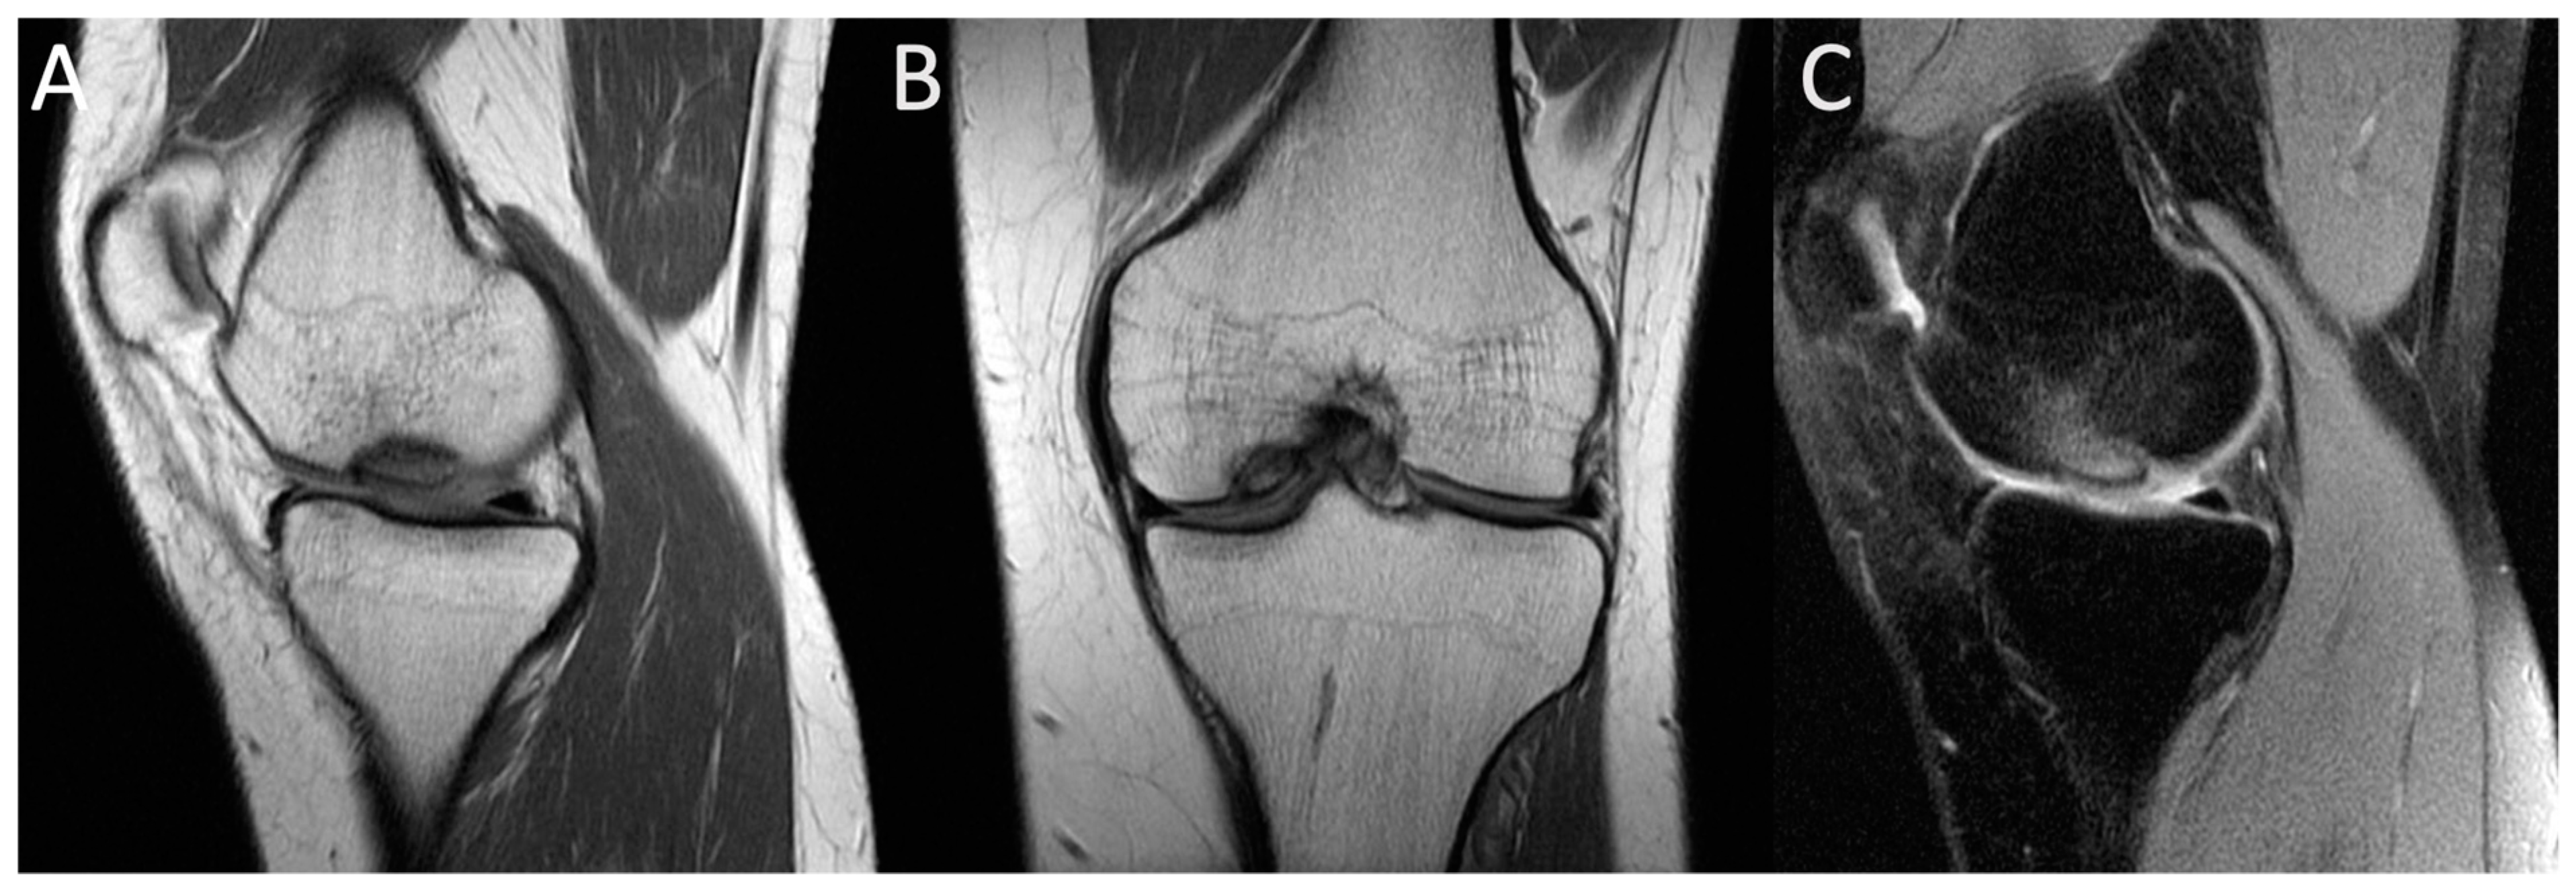

- Accadbled, F.; Turati, M.; Kocher, M.S. Osteochondritis dissecans of the knee: Imaging, instability concept, and criteria. J. Child. Orthop. 2023, 17, 47–53. [Google Scholar] [CrossRef] [PubMed]

- Quatman, C.E.; Quatman-Yates, C.C.; Schmitt, L.C.; Paterno, M.V. The clinical utility and diagnostic performance of MRI for identification and classification of knee osteochondritis dissecans. J. Bone Jt. Surg. Am. 2012, 94, 1036–1044. [Google Scholar] [CrossRef] [PubMed]

| MRI features | T1-weighted images display a single-density, low-signal intensity line. T2-weighted images display a high-intensity line with early necrotic-viable bone interface. | In T1-weighted images, the progeny is typically hypointense. In T2-weighted images, the progeny is mostly heterogeneous; this sequence can assess the integrity of articular cartilage, reactive marrow edema in the parent bone, and fluid or cystic changes at the parent-progeny interface. |